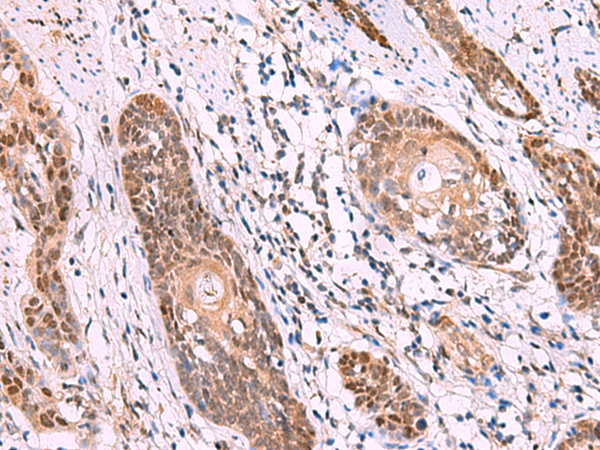

分类: 科研抗体货号: P07187别名: KIP1; MEN4; CDKN4; MEN1B; P27KIP1应用: WB,IHC反应种属: Human, Mouse